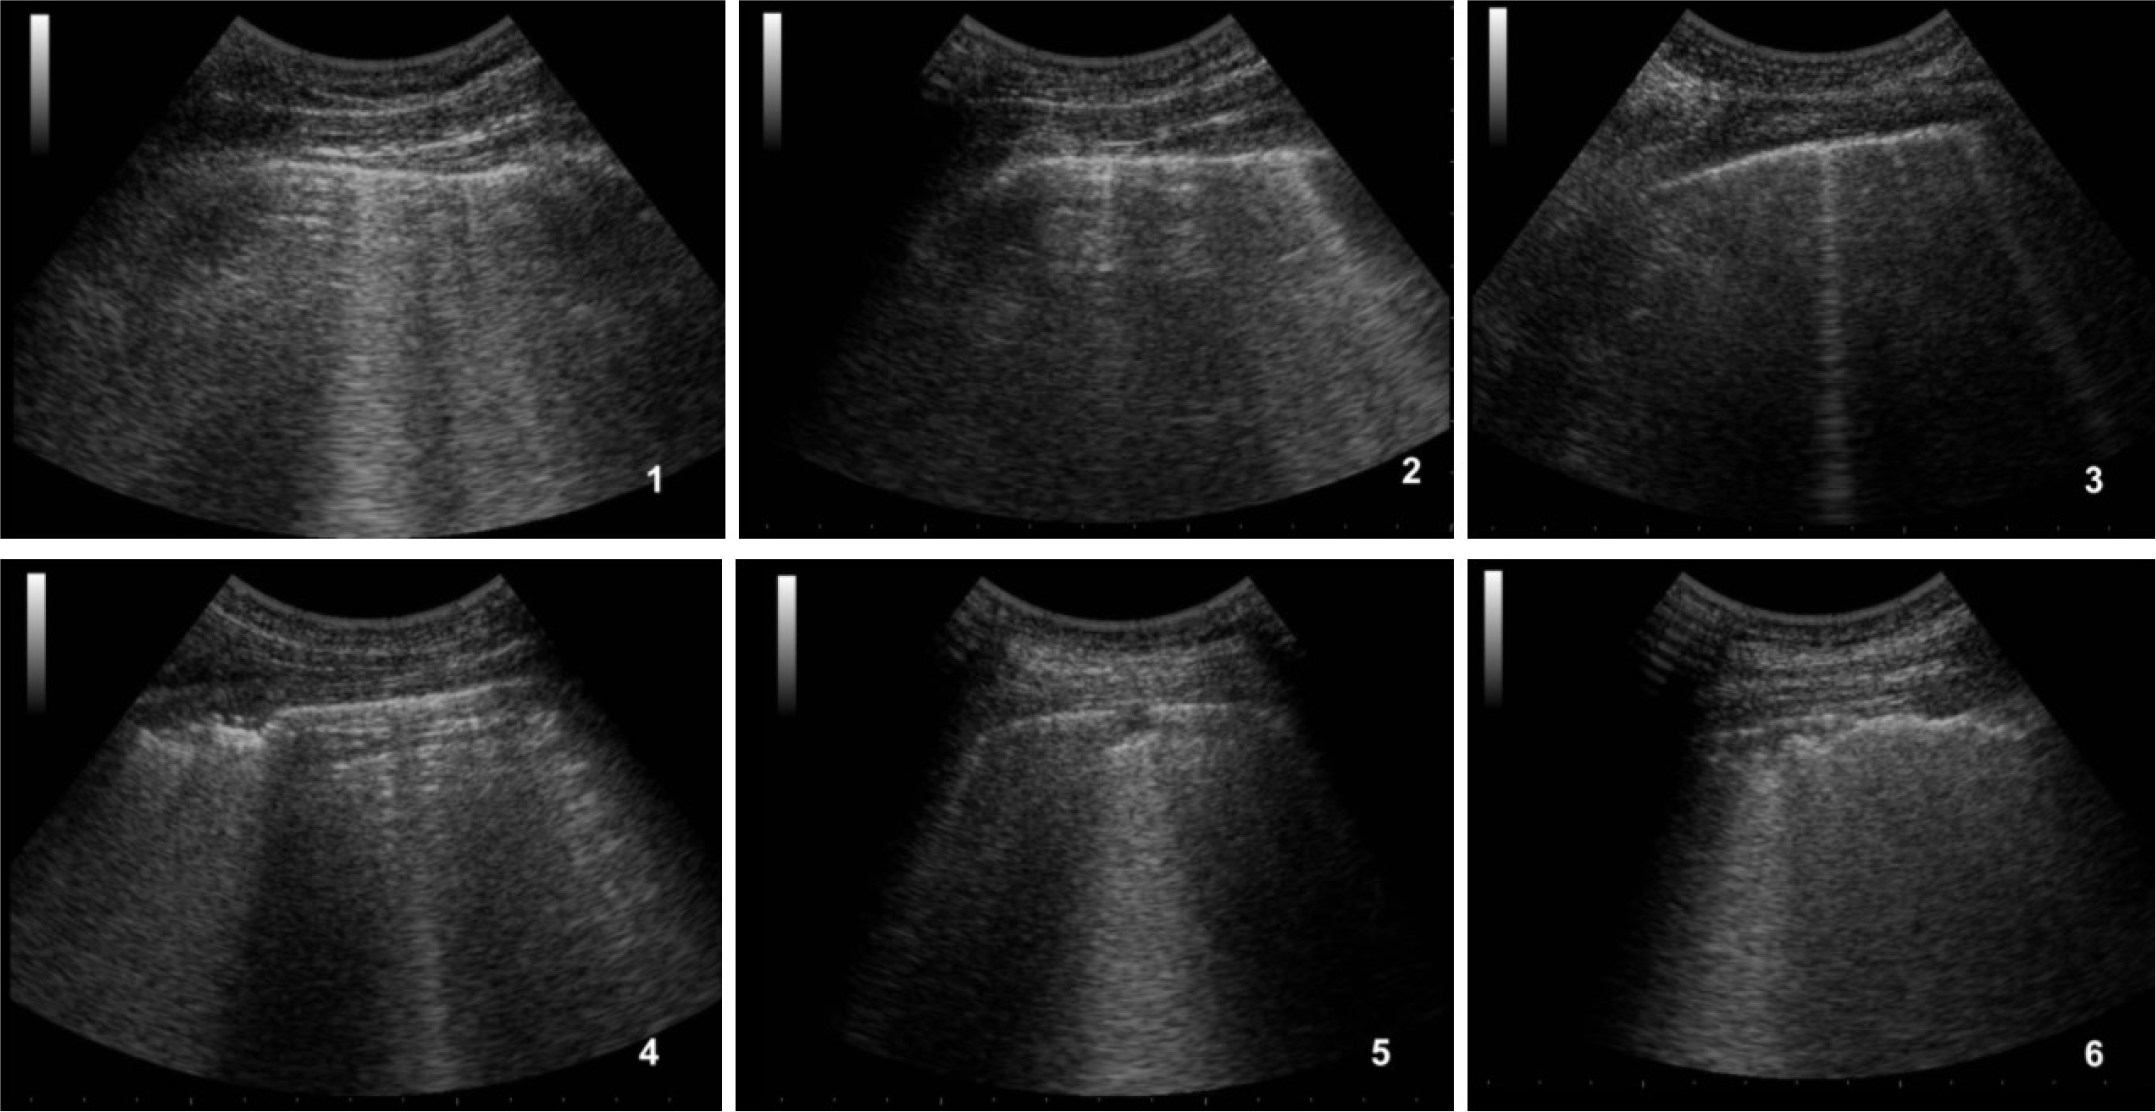

Lung ultrasound showed a suggestive pattern of interstitial lung disease associated with bilateral subpleural consolidations in the postero-inferior scans (Figure 1, 2). The total Lung Ultrasound Score (LUS) was 10. Chest x-ray, performed at the admission, showed a mild thickening of the peribronchovascular interstitium with focal areas of consolidation in the right medio-superior and left medio-inferior regions, compatible with a viral interstitial pneumonia (Figure 3).

Figure 2: Ultrasound of the left lung.

1) antero-superior field with A-lines associated to some B-lines, 2) antero-inferior field with some coalescent B-lines, 3) lateral-superior field with two small B-lines, 4) lateral-inferior field with subpleural consolidations, 5) postero-superior field with a small subpleural consolidation, 6) postero-inferior field with confluent subpleural consolidations associated to fragmented pleural line.